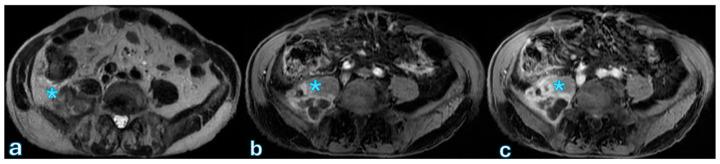

Radiological assessment following pancreaticoduodenectomy is critical for the prompt diagnosis and management of postoperative complications, significantly influencing patient outcomes. Pancreaticoduodenectomy, or the Whipple procedure, is the standard surgical intervention for pancreatic and periampullary malignancies, but it involves notable risks, especially from complications like fistulas, bleeding, or leakage. Cross-sectional imaging, particularly contrast-enhanced computed tomography, serves as the primary diagnostic tool due to its rapid acquisition, high resolution, and effective delineation of postoperative anatomy and complications. Magnetic resonance imaging (with cholangiopancreatography and hepatobiliary contrast agents) complements CT by providing superior contrast resolution for specific complications, notably in the biliary system and pancreatic duct. This narrative review discusses various imaging techniques and their applications, highlighting characteristic radiological features of common postoperative complications. It underscores the importance of a multidisciplinary approach, emphasizing close collaboration between radiologists and surgeons to optimize surgical decision-making and improve patient management post-pancreatic surgery.

胰十二指肠切除术后的影像学评估对于术后并发症的及时诊断和处理至关重要,对患者预后有显著影响。胰十二指肠切除术,即惠普尔手术,是治疗胰腺和壶腹周围恶性肿瘤的标准外科手术,但该手术存在显著风险,尤其是瘘、出血或渗漏等并发症。横断面成像,特别是增强计算机断层扫描,因其采集速度快、分辨率高且能有效描绘术后解剖结构和并发症,成为主要的诊断工具。磁共振成像(结合磁共振胰胆管造影和肝胆对比剂)通过为特定并发症提供更高的对比分辨率来补充CT,尤其是在胆道系统和胰管方面。本叙述性综述讨论了各种成像技术及其应用,突出了常见术后并发症的特征性影像学表现。强调了多学科方法的重要性,强调放射科医生和外科医生之间密切合作,以优化手术决策并改善胰腺手术后的患者管理。